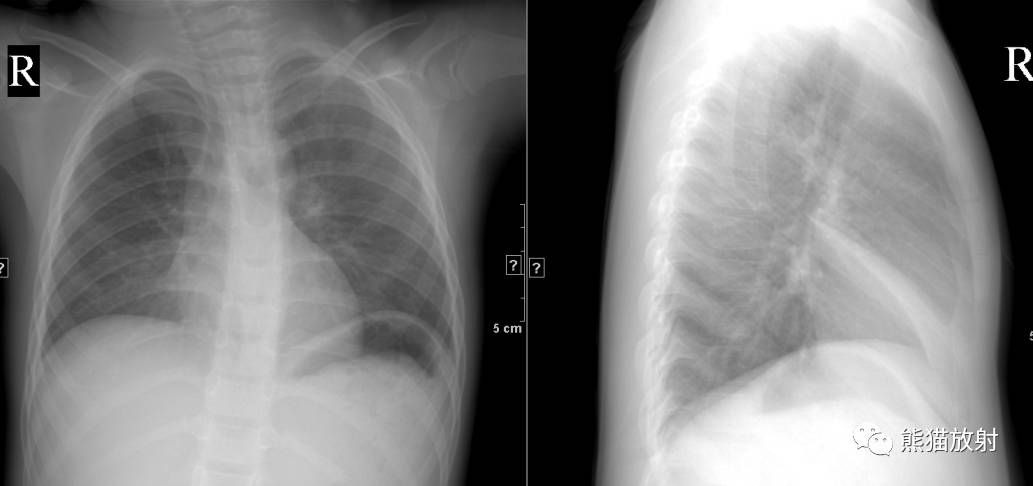

↓ 左肺全肺不张(患者肺野密度增高,胸廓塌陷,气管、纵隔左移) 原因?进一步行CT增强、支气管镜检查。